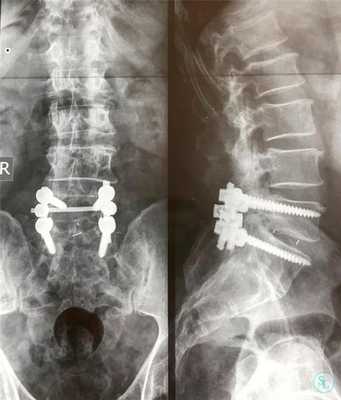

- Устанавливают опорно-стабилизирующие системы (при необходимости).

Стабилизирующие конструкции

Удаление тел, их отростков и других анатомических структур чревато дестабилизацией подвергшегося вмешательству позвоночно-двигательного сегмента, а также повышению риска развития тяжелых прогрессирующих кифотических и сколиотических деформаций. Причем чаще страдает поясничный и шейный отдел, а также в переходные зоны.

Это обуславливает необходимость часто использовать на завершающем этапе операции методики фиксации позвонков. Особенно они важны при выполнении ламинэктомии у детей и подростков, поскольку в таких случаях ситуация усугубляется асимметричным ростом позвонков.

Одним из способов стабилизации прооперированного позвоночно-двигательного сегмента является спондилодез. Его выполнение подразумевает установку специальных опорно-стабилизирующих конструкций, прочно соединяющих соседние позвонки в области воздействия между собой. В определенных случаях дополнительно требуется провести трансплантацию взятого у пациента из подвздошной кости фрагмента. В результате позвонки плотно срастаются между собой и теряют способность двигаться. Но при проведении ламинэктомии на 1 или 2 позвонках и их спондилодезе пациенты обычно не замечают существенных ограничений при движениях.

Современная медицина располагает металлоконструкциями различных типов, что позволяет проводить эффективную стабилизацию. Причем многие из них способны монтироваться таким образом, что в дальнейшем по мере роста ребенка их можно будет удалить.